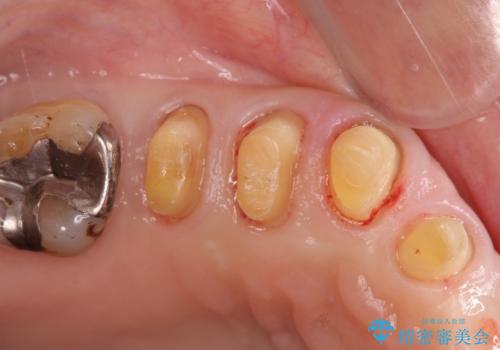

歯周病に対する全体治療

- 近医で「重度の歯周病です、入れ歯にする必要がある。」、と言われ入れ歯以外の方法がないか相談にみえられました。

再生治療、歯周外科を行うことで歯周病治療を行い、残すことのできる歯の歯周環境を整える。

残すことのできない歯は抜去したのち骨造成を含めたインプラント治療を行い、しっかりとした咬合関係を確立していきます。

治療期間はかかりましたが、しっかりと歯周病治療・インプラント治療を行ったおかげで歯周病の状態は非常に良くなり、安定した咬合関係を確立することができました。